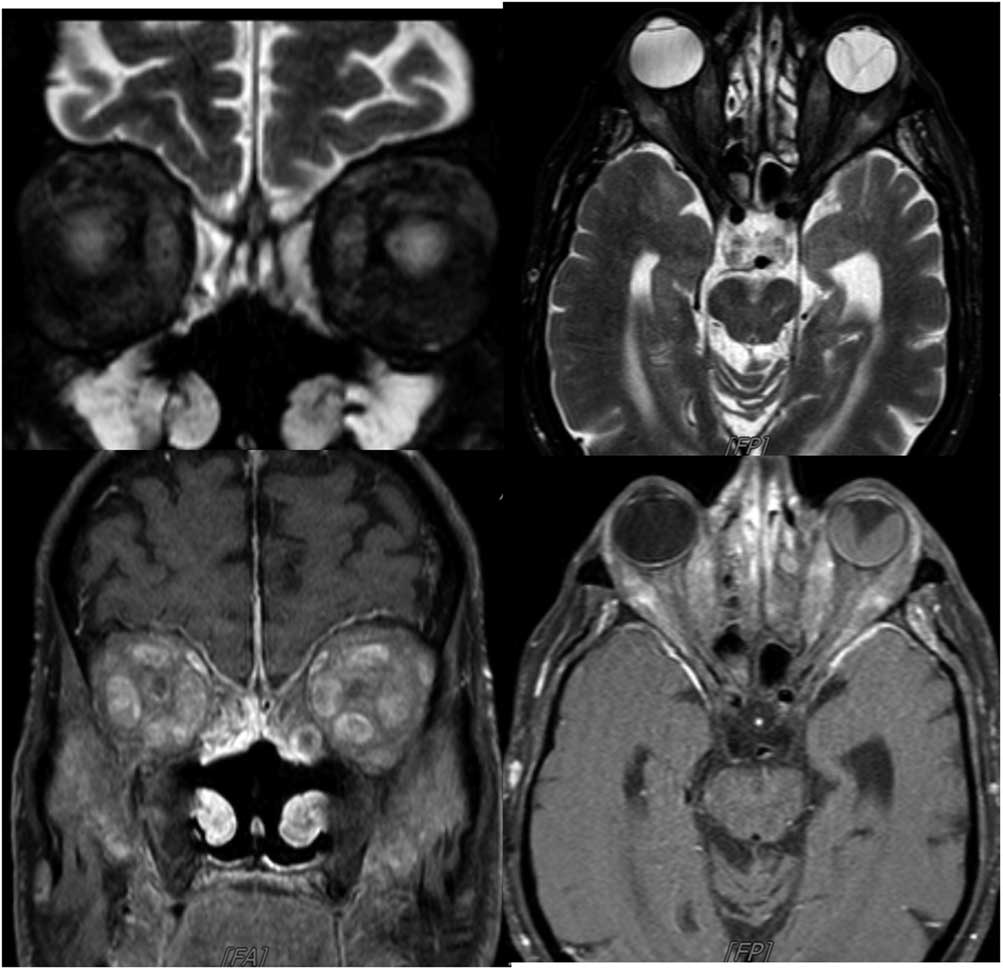

Case 3: A 74-year-old male was admitted with a 1.5-year history of blurred vision and progressive bulging of both eyes. The symptoms started after nasolacrimal duct intubation surgery to treat lacrimal drainage obstruction. He had a past medical history of vision loss in his left eye due to trauma 10 years previous, as well as erosion and perforation of the nasal septum 2 years before. Neurological examination showed bilateral proptosis that was more prominent on his right eye, and his extraocular movements were limited bilaterally in all directions (Figure 3a). MRI of the orbit identified bilateral hyperintensities, enlargement, and contrast enhancement in extraocular muscles. Brain MRI findings included linear dural thickening and enhancement on the anterior frontal and temporal lobes, inflammation and enhancement on the maxillary, frontal, and sphenoid sinuses, and a nasal septum defect (Figure 3b). Investigations revealed a mild increase in CRP and sedimentation rate, slightly low T3 and T4 levels, and normal thyroid-stimulating hormone, CBC, antithyroid antibodies, viral serology, IgG4 levels, ANA, and anti-AChR antibodies. The anti-proteinase ANCA (anti-PR3 ANCA) level was 72.3 U/ml (>20 U/ml), and p-ANCA was found to be positive. Therefore, a diagnosis of orbital inflammation due to GPA was established. Chest CT revealed calcific lung nodules and bilateral apical pleuroparenchymal fibrotic density changes. Histopathological investigation of nasal biopsy revealed chronic inflammation. He was treated with high-dose IV methylprednisolone (1 mg/day for 5 days) followed by 60 mg/day oral prednisolone. He responded with a prompt reduction of proptosis and lid edema and a slight improvement in ocular movement over the 6-month period. Treatment continued with prednisolone tapering and azathioprine.

Figure 3a Patient has bilateral proptosis and bilateral restriction of extraocular eye movements in all directions.

Figure 3b Axial and coronal MRI showing bilateral hyperintensities, enlargement, and contrast enhancement in extraocular muscles, linear dural thickening, and enhancement on the anterior frontal and temporal lobes, enhancement on the maxillary, frontal, and sphenoid sinuses and nasal septum defect. Right bulbus oculi was normal, whereas left bulbus oculi revealed retinal detachment.